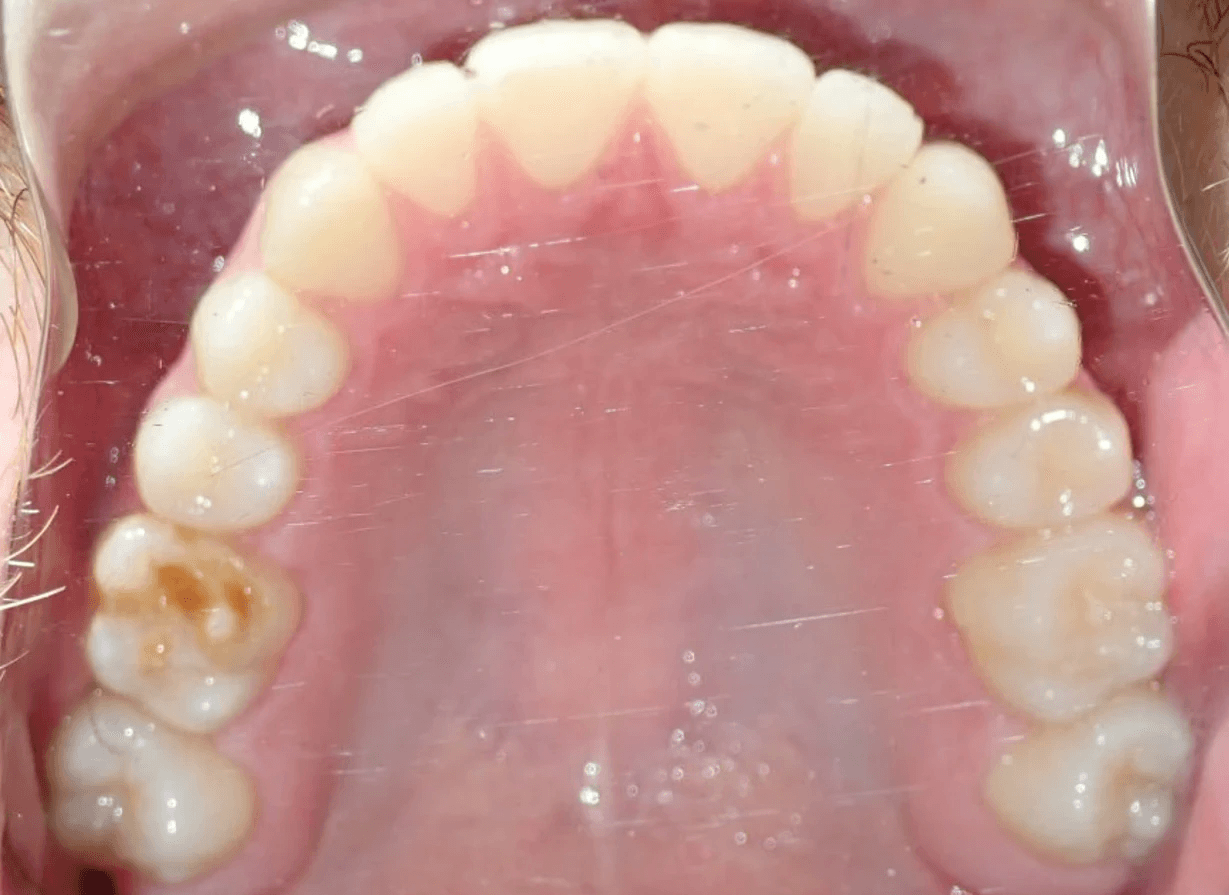

Final results

INTRAORAL